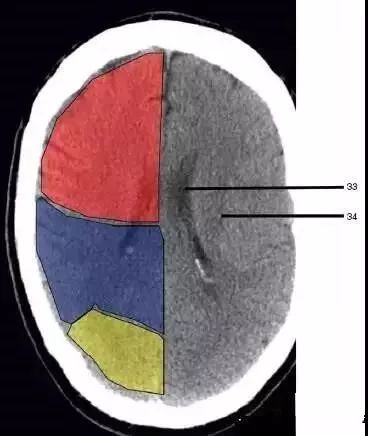

33、侧脑室体部(Body of lateral ventricle)

34、放射冠(Corona radiata):浅红色部分为额叶(Frontal Lobe),黄色部分为枕叶(Occipital Lobe),褐色部分为顶叶(Parietal Lobe)